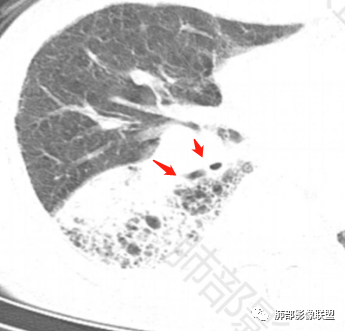

老年男性,反复咳嗽咳痰喘憋8年,加重10天,发热半天。白细胞计数明显升高(存在细菌感染可能),CEA、CA19—9升高(肺癌或间质性肺疾病引起可能)。痰培养见肺克。CT;双肺弥漫小叶间质、中轴间质增厚,胸膜下肺气肿,右肺门及右下叶可见实变影,边界模糊,内支气管走形僵硬,部分见蜂窝样改变,增强后实变区可见低密度区(粘液?),叶间裂膨隆,纵隔及右肺门见肿大淋巴结,右肺门淋巴结内见坏死。存在感染,但单纯感染难以解释支气管走行僵硬、实变内的低密度病灶,考虑恶性伴感染,肺炎性肺癌或黏液腺癌。

2.影像表现:肺气肿背景,右肺下叶呈现明显网格影及蜂窝影、枯枝征,边缘膨隆、叶间裂向前方推移。病灶密度不均,前份见不规则片状实性密度区,实性部分轻度强化,边界不清,周边特征掩盖不清。支气管主要分支显示,呈枯枝征。纵隔窗病灶密度偏低,病灶内血管影边缘稍显模糊,未见明显液化坏死区。

右侧肺门淋巴结肿大,中央低密度;纵隔见轻度增大淋巴结。

3.综合分析:临床方面:慢性病程、急性发作,呼吸道症状伴发热,炎性指标升高,提示存在感染可能;CA199升高,但相对特异性不高。影像双肺气肿,右肺下叶蜂窝状改变明显,夹杂实变密度区,支气管相关但未见阻塞,较常见于感染性病变,如G-杆菌感染等。蜂窝影什么时候出现我们不得而知,实变区周边特征掩盖不清。

因为有肺气肿背景、有蜂窝,周边特征及张力等都不能作为判断依据或参考。单肺叶蜂窝影伴实性密度区被确诊为肺腺癌的例子已不少见,敬请留意。

如本例片影长期不散以及肺门异常增大淋巴结是本例怀疑肺炎型肺癌的理由。